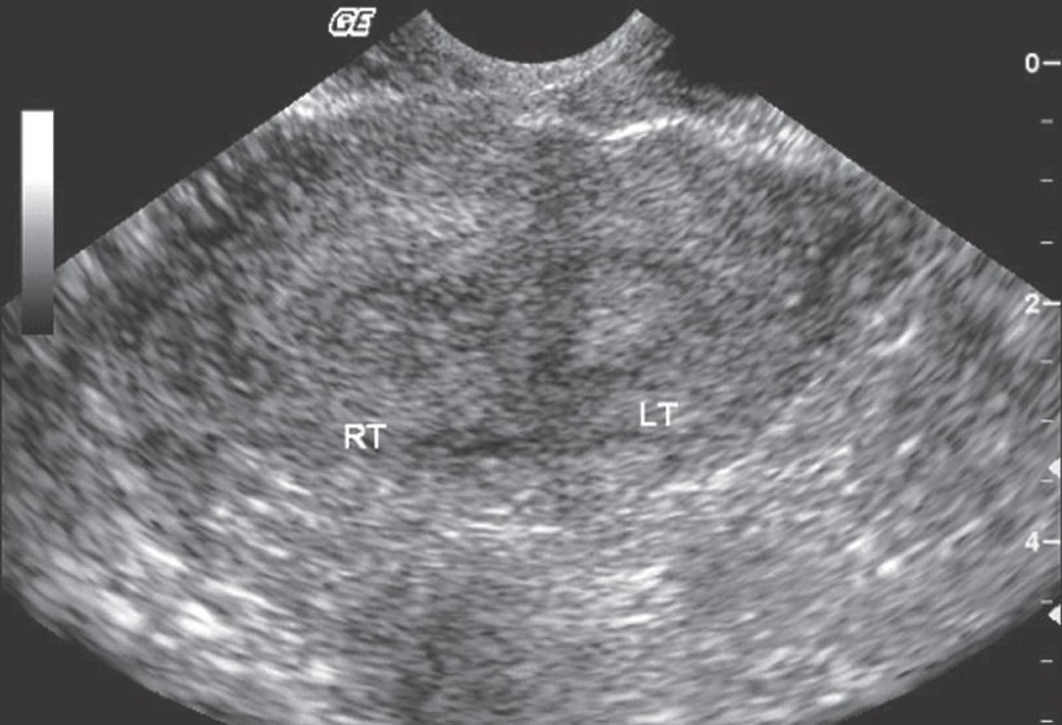

Uterus w/ Fibroids

submucosal fibroids